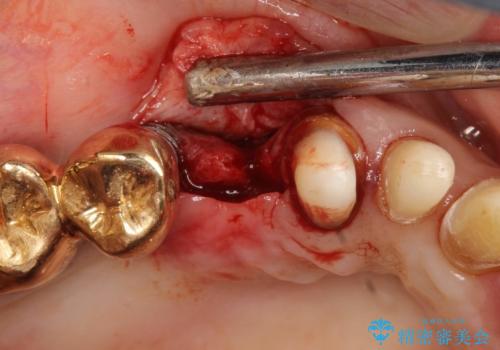

- 破折により保存不可能となった歯を抜歯後、待時してインプラントを計画した。

骨が薄く、インプラントの径に耐え得ないと判断したためスプリットクレストにより骨幅を拡大しインプラントを埋入した。

スプリットクレストやリッジエキスパンジョンといった方法は、骨が薄く、細い場合に、割線を設定し、狭い骨幅を拡大すると同時にインプラントを埋入することができます。